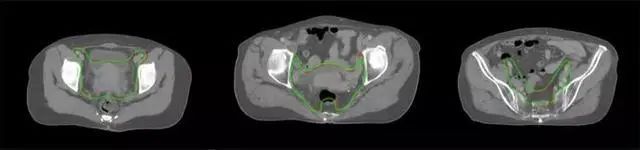

四、放射治療智能勾畫軟件

產(chǎn)品背景

放射治療,簡稱放療,是治療腫瘤主要手段之一,利用放射線破壞照射區(qū)(靶區(qū))的細(xì)胞,使腫瘤細(xì)胞停止分裂直至死亡,醫(yī)生通常把放射治療形象的比喻為“打靶”,放療前精準(zhǔn)勾畫腫瘤靶區(qū)范圍是腫瘤放射治療的關(guān)鍵步驟。傳統(tǒng)的靶區(qū)勾畫醫(yī)生會(huì)根據(jù)患者多張CT、MRI影像片憑借經(jīng)驗(yàn)進(jìn)行,比較耗時(shí),治療的病人數(shù)量也有限,且靶區(qū)勾畫缺少行業(yè)統(tǒng)一的規(guī)范和標(biāo)準(zhǔn),無法達(dá)到同質(zhì)化,勾畫精確度不理想。

技術(shù)原理

基于深度學(xué)習(xí)人工智能的放療靶區(qū)智能勾畫技術(shù)和自動(dòng)計(jì)劃技術(shù),基于全面的市場調(diào)研和臨床專業(yè)意見,采用獨(dú)創(chuàng)的基于小樣本量的人工智能算法,實(shí)現(xiàn)放療靶區(qū)和危及器官的快速全自動(dòng)勾畫。

產(chǎn)品優(yōu)勢

縮短至幾分鐘內(nèi)便可完成,大幅提升了放療效率,且人工智能平臺(tái)完成的靶區(qū)勾畫可基本滿足臨床醫(yī)生需求,專家只需審核時(shí)細(xì)微調(diào)整,可顯著提高靶區(qū)勾畫的規(guī)范化及精準(zhǔn)度,讓放療智能化,標(biāo)準(zhǔn)化。可覆蓋食管癌、鼻咽癌、直腸癌、宮頸癌、肺癌等多種病種。